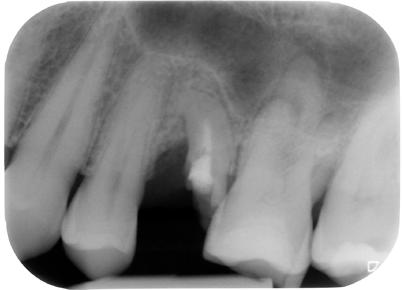

8. ábra: A műtét előtti röntgenfelvétel a 45-ös és 46-os fogat érintő súlyos szuvasodási folyamatokat mutatja.

ábra: A kezelési terület izolálása érdekében kofferdám került felhelyezésre. A szuvas foganyag eltávolítását követően körkörös matricákat helyeztünk fel az endodonciai csonkfelépítés érdekében. – 10. ábra: A hiányzó falak kiépítése. – 11. ábra: A 45-ös és 46-os fog előkészítve és megtisztítva, készen állnak a gyökércsatorna-rendszer betömésére.

kutatunk [6]. A fenti faktorok mind hatással vannak a fog várható prognózisára. Az üreg teljes körű megtisztítása lehetővé teszi, hogy szükség esetén szabályszerűen el tudjuk végezni az endodonciai csonkfelépítést, amely a későbbiekben a kofferdámizolálás felhelyezhetőségét biztosítja. Amenynyiben lehetőségünk van rá, akkor minden esetben törekedjünk végleges endodonciai csonkfelépítés készítésére. Ez jelentős mértékben megkönnyíti az endodonciai kezelések kivitelezését és hozzájárul a gyökércsatornarendszer fertőtlenítésének szakszerű kivitelezéséhez. Az endodonciai csonkfelépítés elvégzésére fordított idő többszörösen megtérül a fog – gyökértömés elkészítését követően végzett – végleges felépítése során, mivel ekkor már gyakorlatilag egy minden oldalról ép falakkal körülvett üreg feltöltését kell csak elvégeznünk (8–12. ábrák).

ábra: A jobb alsó kvadráns helyreállítása után készült röntgenfelvétel.